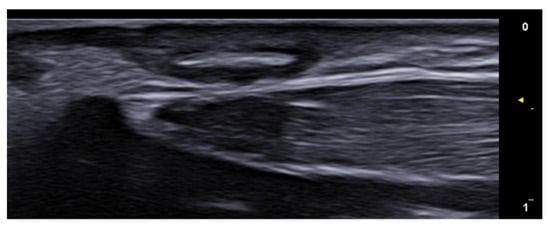

- Cataldo-Cerda, K.; Wortsman, X. Dissecting Cellulitis of the Scalp Early Diagnosed by Color Doppler Ultrasound. Int. J. Trichology 2017, 9, 147–148. [Google Scholar] [CrossRef]